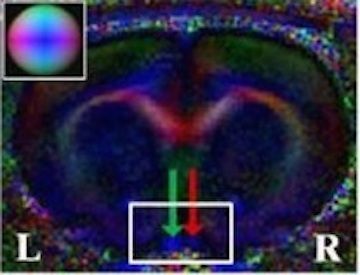

• Selective Deletion of NBCe1 in Reactive Astrocytes Attenuates Ischemic Stroke Brain Damage

• Capuk O, Berthold E, Kaliyappan K, Avunoori M, Muduganti R, Krishna S, Metwally S, McFarland M, Song S, Fiesler V, Fischer S, Foley LM, Hitchens TK, Waxman S, Sigal IA, Theparambil SM, Begum G.

• Glia, 73(12), 2386–2406. https://doi.org/10.1002/glia.70075